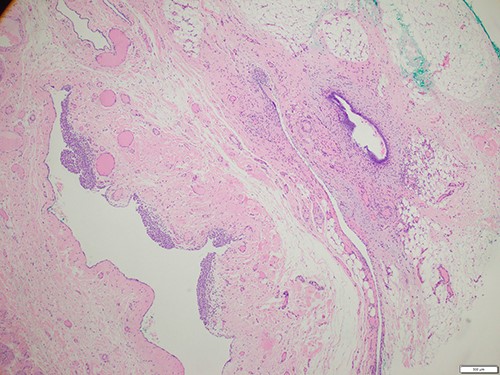

The patient was referred for an ultrasound (US) of the left groin, which showed a contained cyst in the inguinal canal consistent with a CCN (Fig. 1). She was referred to a general surgeon for elective surgical management. A herniorrhaphy was performed with excision of the canal of Nuck and mesh repair. The procedure occurred without complication and the patient was discharged the following day. Histopathology report confirmed a CCN as well as evidence of endometriosis in the adjacent tissue (Fig. 2).

Histology of the surgical specimen (×40 magnification) shows a cystic structure lined in part by cuboidal epithelium in keeping with a cyst of canal of Nuck; focal endometriosis is identified in the adjacent soft tissue.